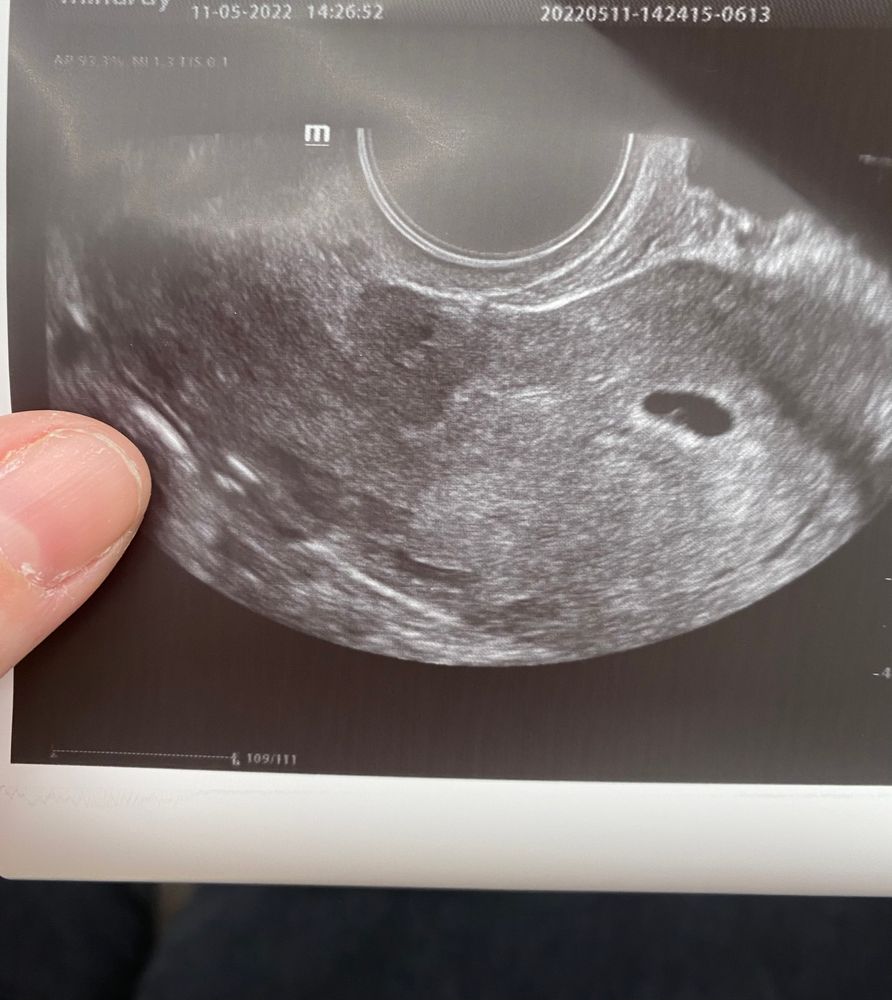

И там же сделала узи чуть позже на 3-4 неделе, плодное яйцо в полости матки увидели (маленькая миленькая точечка)

узи от 11 мая